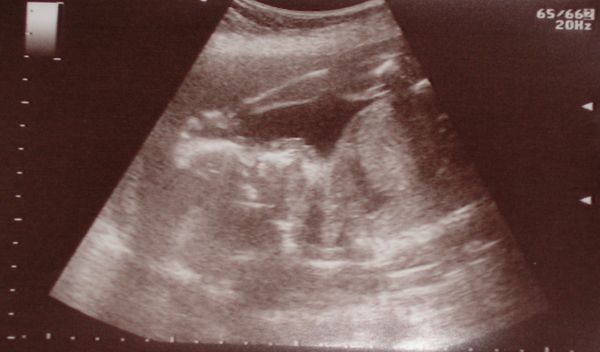

Első Milos Zétény (boy=fiú :wink: )

A második képen fent a keze látható Zetinek (Edus Milosnak, Zsiga Májlónak, Zsombi meg csak egyszerűen hööö-nek hívja), és fogja a buksiját. Gondolkodik, tehát van.